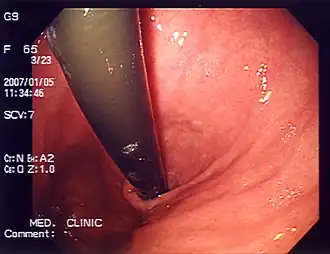

Diagnostic investigations for the evaluation of heartburn include endoscopy and esophageal pH monitoring. GERD is commonly diagnosed based on symptoms of heartburn or regurgitation. Endoscopy may be used to evaluate people who do not respond to treatment for heartburn or those with alarm symptoms such as persistent vomiting, gastrointestinal bleeding, iron-deficiency anemia, involuntary weight loss, difficult/painful swallowing (dysphagia, odynophagia), epigastric mass, family history of esophageal or gastric cancer, and new onset of symptoms in those older than 50 years of age.[23]

Endoscopy is a method used to detect abnormalities in the esophageal lining such as erosive esophagitis and Barrett's esophagus. Biopsies taken during an endoscopy can help assess for other conditions linked to heartburn, such as eosinophilic and lymphocytic esophagitis.[14] The esophageal 24-hour pH test or the multichannel intraluminal impedance-pH test is often performed in those with refractory heartburn who have undergone an endoscopy. High-resolution esophageal manometry (HREM) is the standard test for diagnosing esophageal motor disorders. It helps rule out major motility issues in those with persistent heartburn who have normal endoscopy and pH testing. Motility disorders include achalasia, esophagogastric junction outflow obstruction, diffuse esophageal spasm, jackhammer esophagus, and absent contractility. HREM can also distinguish GERD from conditions like rumination and supra-gastric belching. In some cases, gastric scintigraphy may be used to detect gastroparesis.[24]